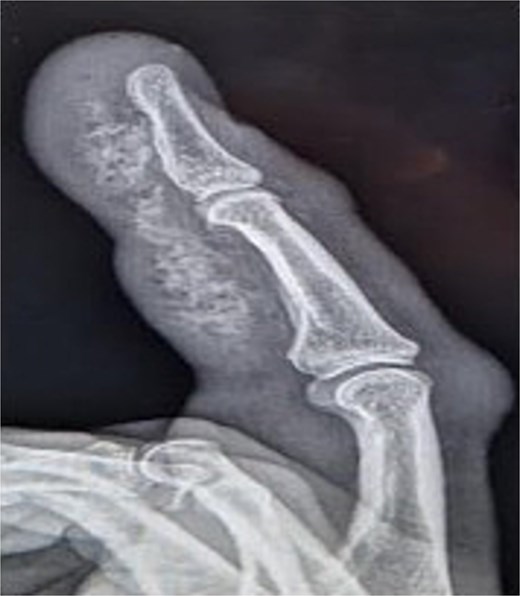

Initial presentation (Fig. 1) with accompanying X-ray (Fig. 2) and intra op image during first debridement (Fig. 3).

X-ray image of patient one showing injected material into volar surface of his digit.